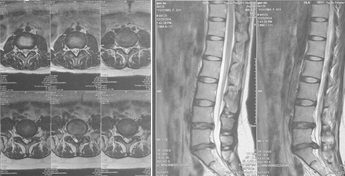

腰椎MRI示:L5S1椎间盘突出,左侧神经根受压。

(图)术前MRI